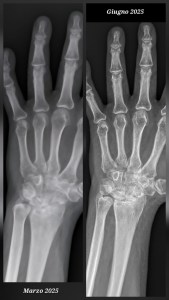

Evoluzione funzionale dopo frattura bilaterale dei metacarpi: gestione riabilitativa della QMR Therapy

La Qmr Therapy ha recuperato la funzionalità, eliminando Artrosi al polso